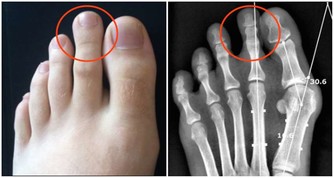

紅辣椒花椒水

功效:淤積濕寒的風濕性關節炎

1、干紅辣椒25 個,花椒30 克。

2、花椒加水3000 毫升,文火煎半小時,放入紅辣椒煮軟取出,去籽。

3、將辣椒皮撕開,貼於患處,共貼三層(可用紗布綁住),敷10 分鐘左右(可根據自己的忍耐程度縮短敷治的時間)。

4、每晚敷1 次,連敷1 週。

注:連續用的花椒水中,放入的辣椒皮必須每次更新。